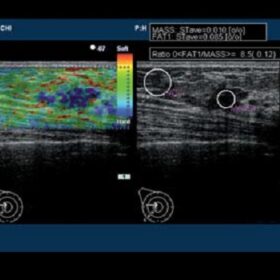

Ultrasound EUB-7500HV – Image Gallery

- Hitachi Real-time Tissue Elastography (HI-RTE)